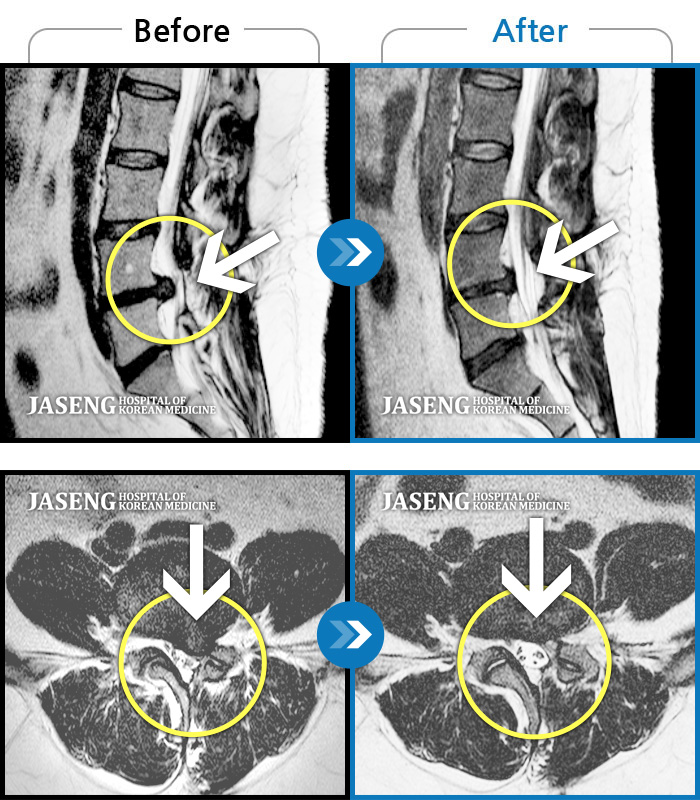

허리디스크

인천 · 조남훈 원장

허리가 너무 아프고 다리가 저려요.

촬영시기

2018.04.23 ~ 2025.12.05

2025.12.19